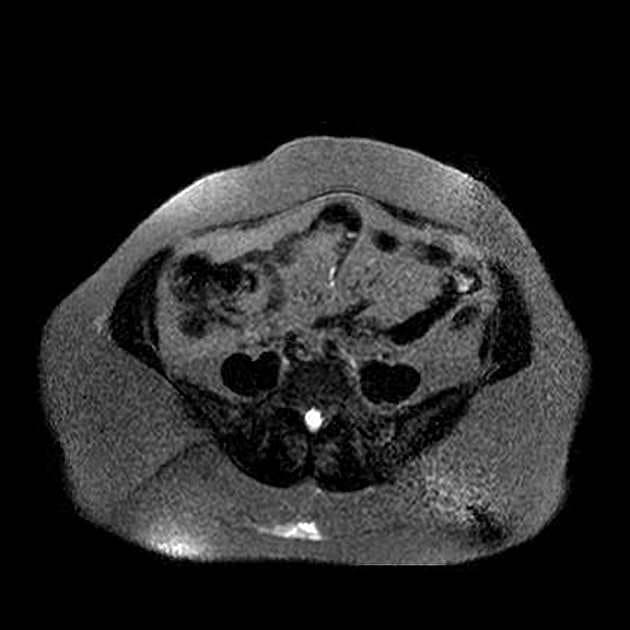

- Tổn thương dạng thùy (lobulated) kích thước 35 x 45 mm nằm ở phân đoạn V của thuỳ phải, liền kề với túi mật (gallbladder).

- Trên hình ảnh cộng hưởng từ có tiêm thuốc tương phản động (dynamic contrast-enhanced imaging), thấy tăng quang dạng nốt (nodular) ở vùng ngoài viền (peripheral) ban đầu, tiếp theo là quá trình lấp đầy dần từ ngoài vào trong (slow centripetal filling).

U sợi mạch gan là khối u gan lành tính phổ biến nhất, thường được phát hiện tình cờ trên hình ảnh học. Bệnh xuất phát từ các mạch máu bất thường và gồm các khoang giãn chứa đầy máu được lót bởi tế bào nội mô. Trên cộng hưởng từ (MRI), hình ảnh điển hình bao gồm tăng tín hiệu rõ rệt trên T2 và kiểu tăng quang dạng nốt ở vùng ngoại vi trong thì động mạch, tiếp theo là quá trình lấp đầy dần từ ngoài vào trong ở các thì muộn. Dấu ấn hình ảnh này rất đặc hiệu, cho phép chẩn đoán chắc chắn không xâm lấn trong hầu hết các trường hợp. Mặc dù có thể sinh thiết, nhưng thủ thuật này tiềm ẩn nguy cơ chảy máu và thường được tránh. Điều trị mang tính bảo tồn, không cần cắt bỏ hay theo dõi định kỳ trong các trường hợp điển hình, trừ khi có nghi ngờ chẩn đoán hoặc bệnh nhân có triệu chứng.